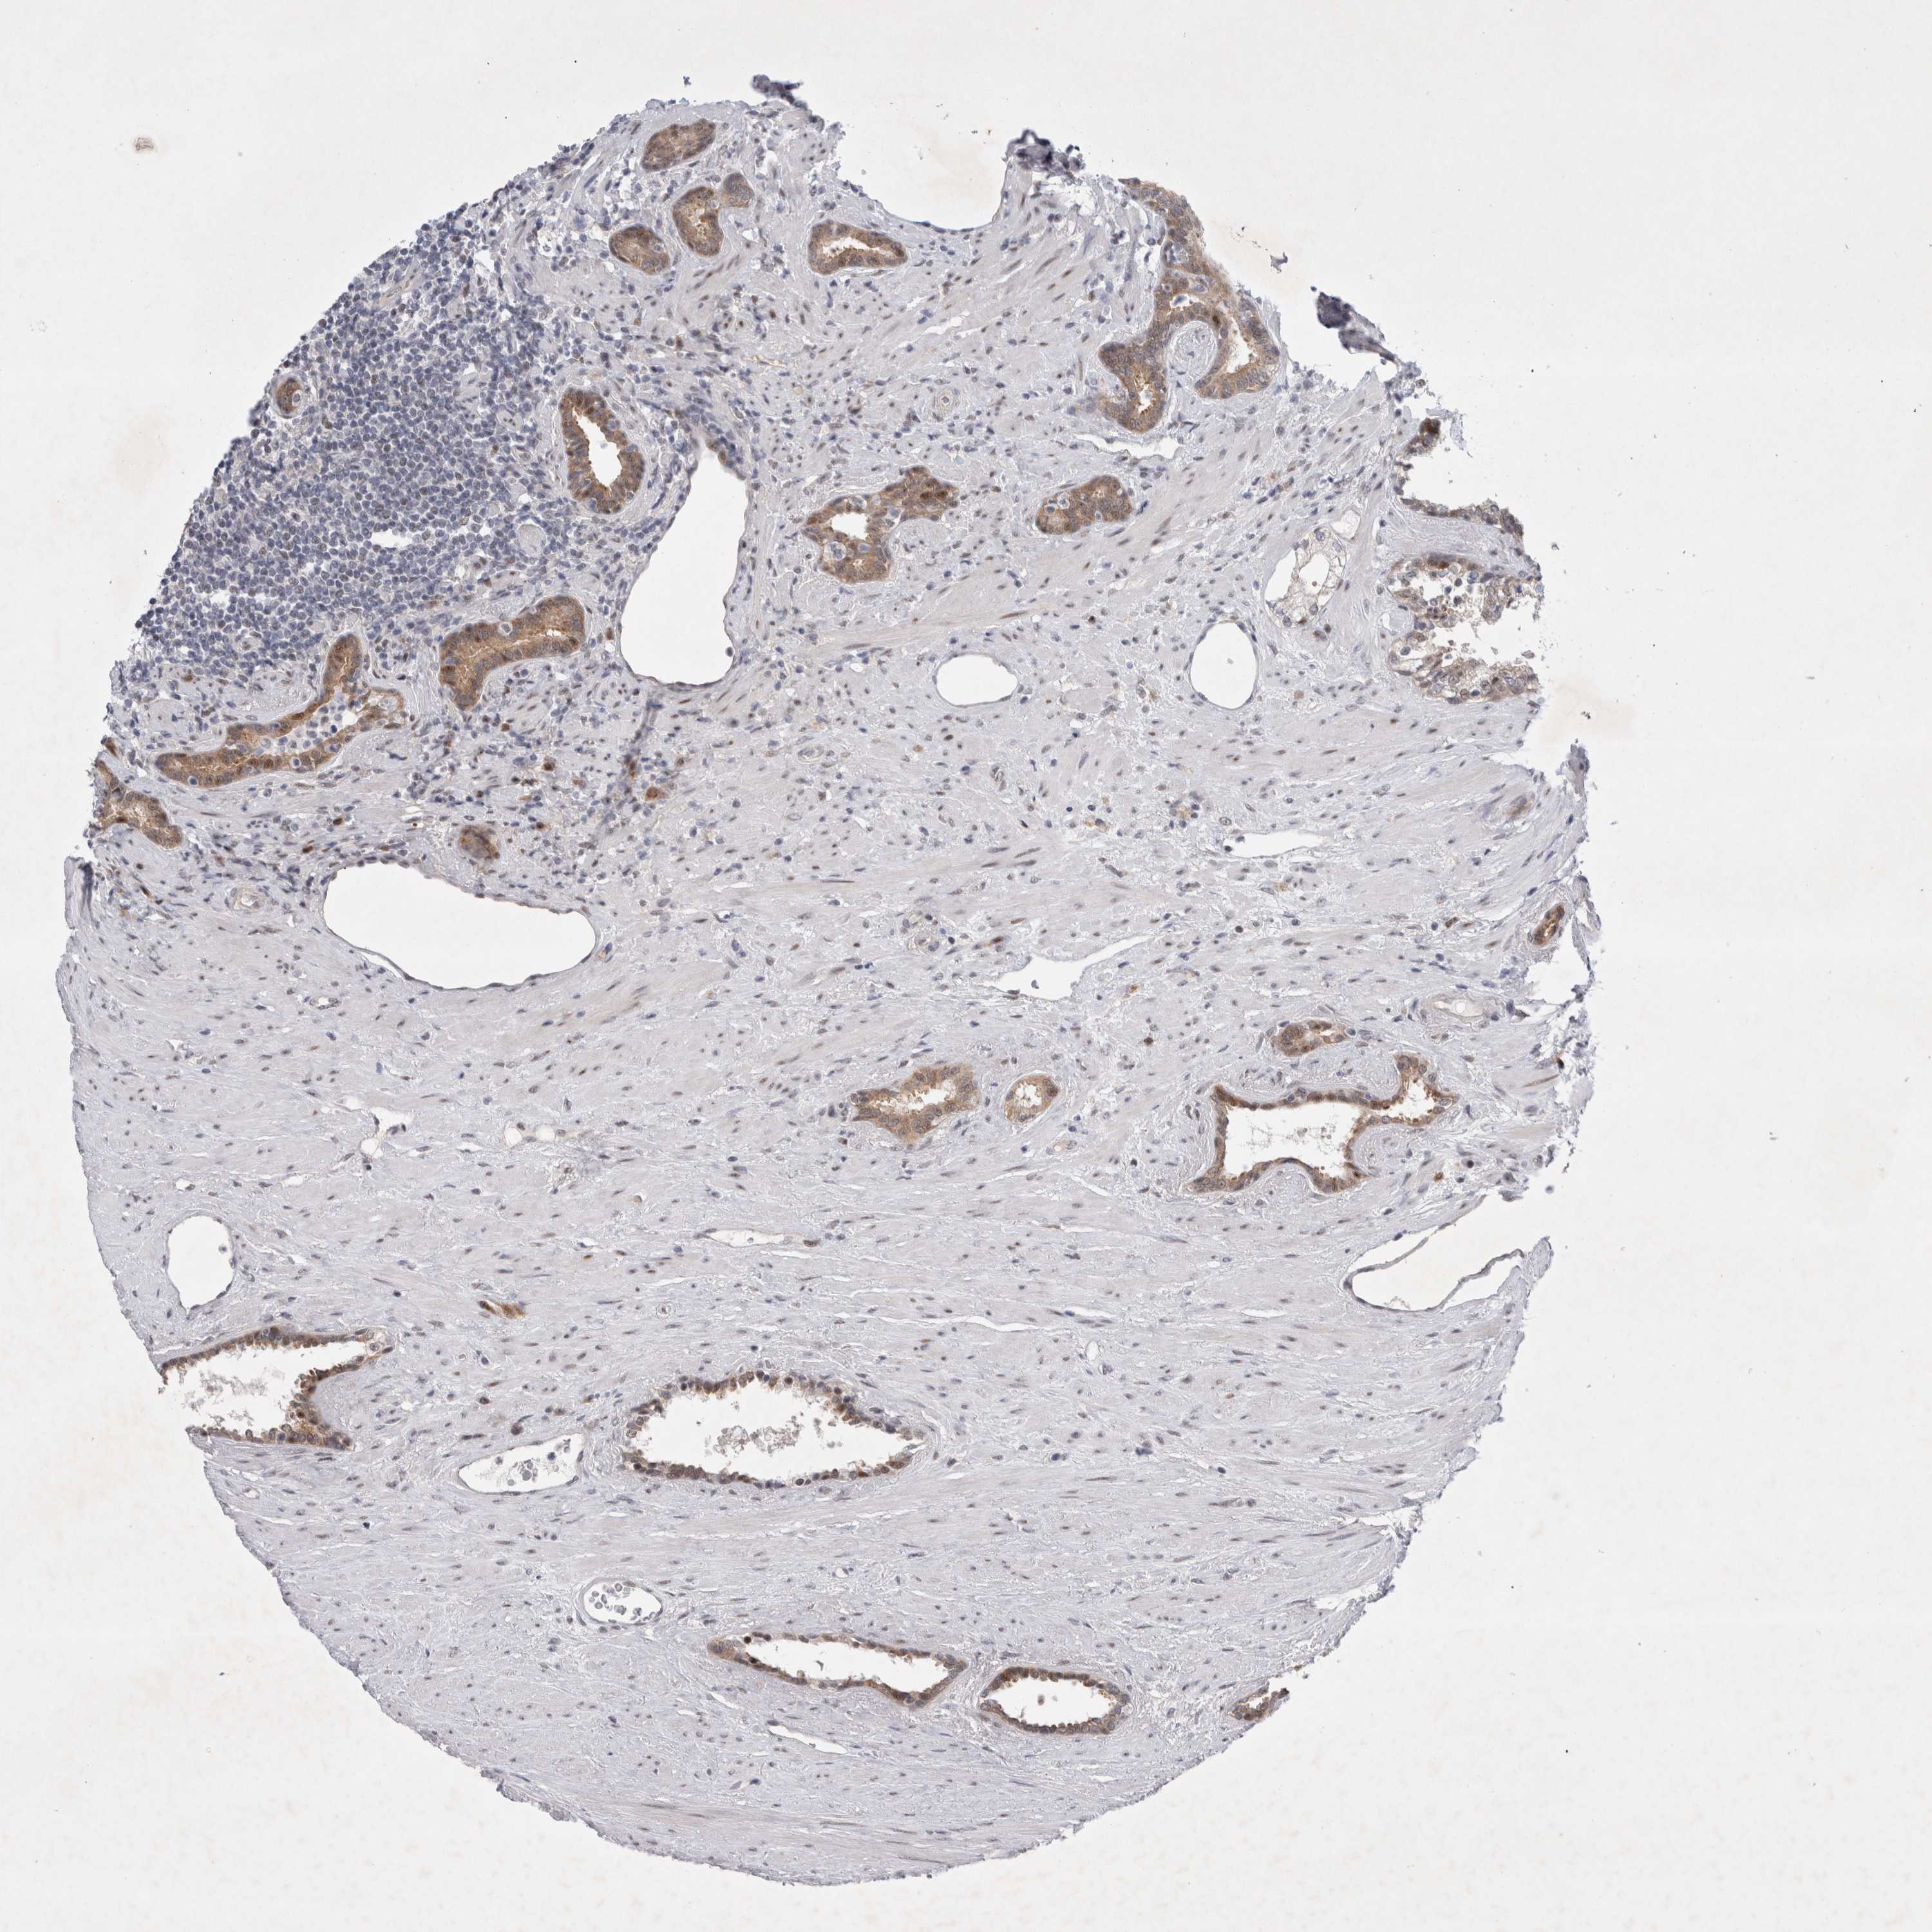

PROSTATE CANCER - Protein expressioni

A mouse-over function shows sample information and annotation data. Click on an image to view it in a full screen mode. Samples can be filtered based on level of antibody staining by selecting one or several of the following categories: high, medium, low and not detected. The assay and annotation is described here.

Antibody stainingi

Antibody staining in the annotated cell types in the current human tissue is reported as not detected, low, medium, or high, based on conventional immunohistochemistry profiling in selected tissues. This score is based on the combination of the staining intensity and fraction of stained cells.

Each image is clickable and will lead to virtual microscopy that enables deeper exploration of all samples and also displays staining intensity scores, fraction scores and subcellular localization as well as patient and tissue information for each sample.

Antibody HPA024000

Antibody HPA024001

Antibody HPA024467

Staining

High

Medium

Low

Not detected

Intensity

Strong

Moderate

Weak

Negative

Quantity

>75%

75%-25%

<25%

None

Location

Nuclear

Cytoplasmic/membranous

Cytoplasmic/membranous,nuclear

Adenocarcinoma, High grade

Adenocarcinoma, Low grade